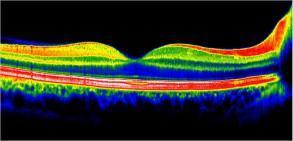

OCT maculaire

Qu'est ce que c'est un OCT de la rétine maculaire ?

L'OCT ou Optical Coherence Tomography est une Tomographie à cohérence optique.

Il permet de dépister les maladies rétiniennes sur la zone centrale de vision nommée macula : un œdème de la rétine, des néovaisseaux, une atrophie, une membrane épi-rétinienne, un trou maculaire, une atteinte de la DMLA, du diabète, ou encore les conséquences d'une occlusion veineuse...

L’image est obtenue par l'émission d'un faisceau laser de faible énergie réalisant des images représentant des coupes des différentes couches de la rétine.